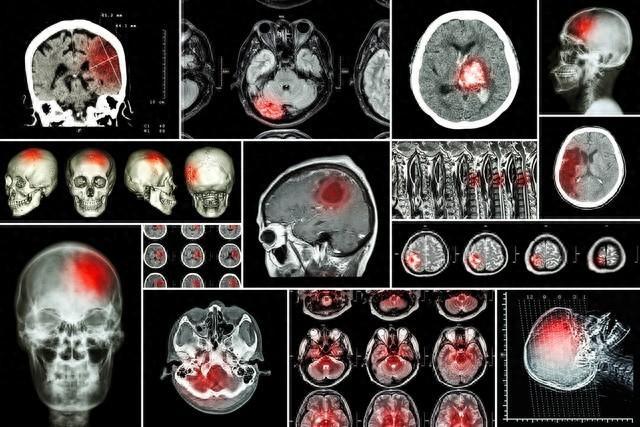

腦梗死,又被稱爲腦梗塞,簡單地解釋就是大腦中的血管出現了堵塞,導致腦組織壞死。可以說,腦梗死的危害相當顯著,最可怕的就是偏癱甚至猝死的發生。無論是致殘率還是死亡率,腦梗死都很高。

此外,腦梗死作爲突發事件之一,即使及時搶救,也會給患者的身體留下不同程度的後遺症。在腦梗死的潛伏期,我們的體內可能會出現有這種疾病的“警告”信號。如果能及時發現並採取適當的應對措施,或許就能挽救自己的生命,並預防腦梗死的問題變得更嚴重。因此,重視腦梗死的早期預警,及時發現並採取措施,對腦梗死的防治來說具有重要意義。